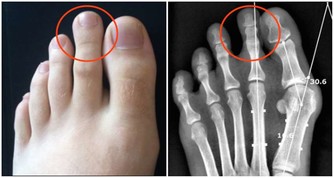

相信大家應該都有去看過牙醫補過牙的經驗,但除了那令人發毛的機械聲之外,

你可曾想像過醫生是怎麼幫你的牙齒美化的嗎?

不知道,那就一起來看看這段充滿另類療愈感的補牙畫面吧!

原來醫生補牙的過程長這樣,

看來下次補牙如果會害怕,那就一直想著這個畫面來轉移注意力吧!